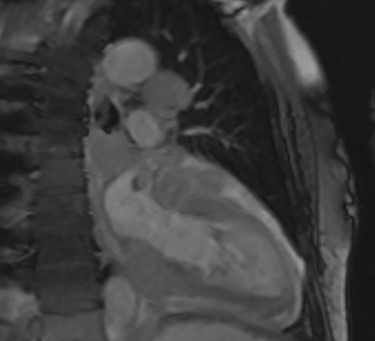

This demonstrated a bulky mediastinal tissue (measuring 50% of the heart) that encased all the aorta and pulmonary artery as well as the coronary artery. It has malignant behaviour with multiple foci that breached fascial planes. It restricted the long axis of the heart but was not causing haemodynamic occlusion. It was non-resectable.

Cardiac MRI (sagittal plane) showing the lesion encasing the aorta, pulmonary artery and all coronary arteries of the heart.